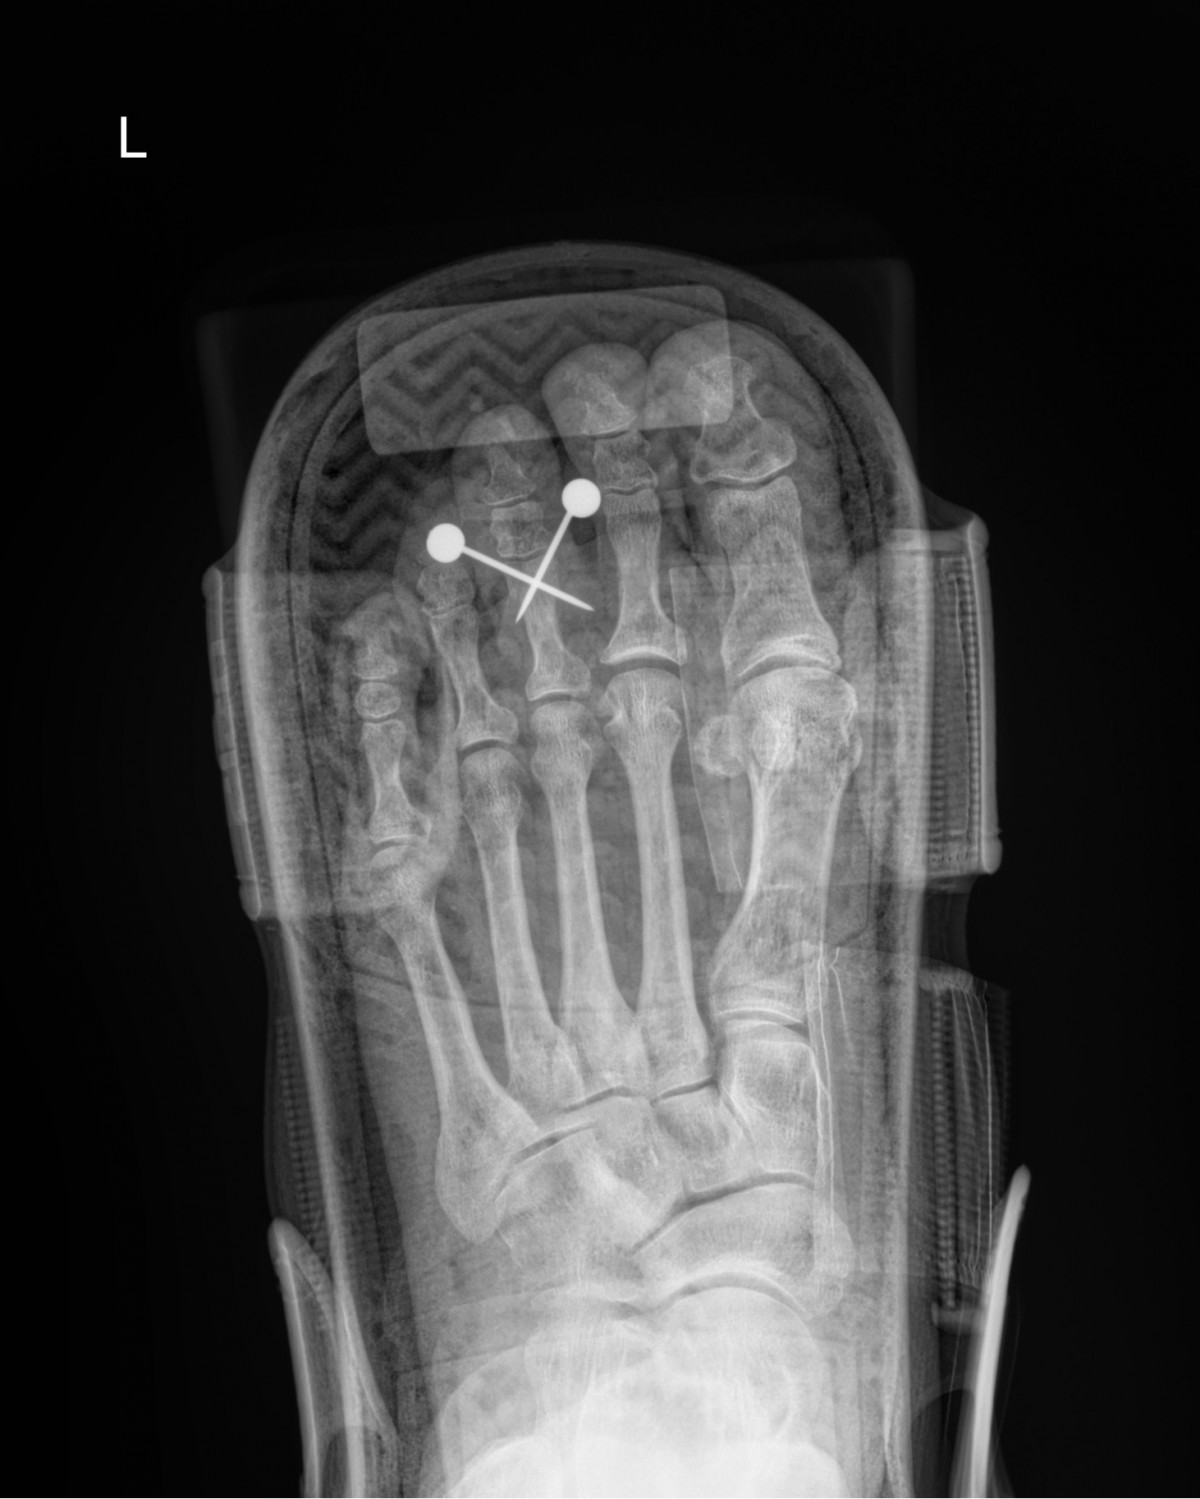

정지영원장님 발가락 골절 수술 이금O 환자

dae765e4d9ac96aee867c9d6292d8784_1758008573_5122.jpg